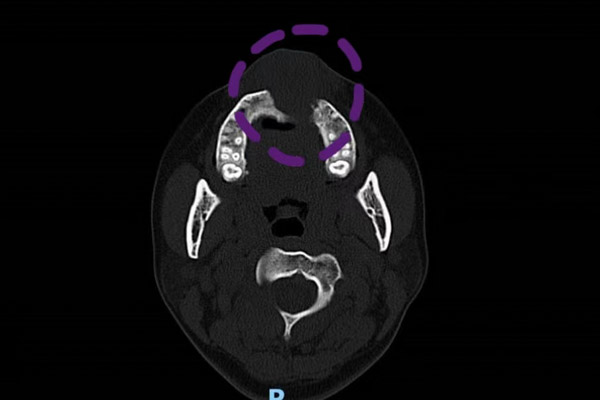

但是為了根除惡性腫瘤,切除手術(shù)是無(wú)法避免的,為了最大程度的保住患者容貌,口腔科、耳鼻咽喉科、麻醉科多學(xué)科共同商討方案,最終決定通過(guò)多期手術(shù)的方式來(lái)達(dá)成“保臉”的目的。先進(jìn)行切除手術(shù)并使用“門(mén)型”瓣修復(fù),待患者腫瘤痊愈且無(wú)復(fù)發(fā),再進(jìn)行贗附體修復(fù)術(shù)對(duì)手術(shù)切除的骨骼進(jìn)行替代。

通過(guò)科內(nèi)激烈討論,最終確定了采用下唇Abbe轉(zhuǎn)移修復(fù)上唇,延長(zhǎng)上唇,重建上唇人中處形態(tài);兩側(cè)唇弓采用粘膜V-Y推進(jìn)瓣,將口腔內(nèi)粘膜推出制作紅唇粘膜,并制作出贗復(fù)體,支撐面部外形,修復(fù)腭部缺損的手術(shù)方案。

手術(shù)非常成功,贗復(fù)體代替了缺損骨科支撐起了面部外形,紅唇粘膜也被重新修復(fù),為下一步的治療創(chuàng)造了有利的條件。曾女士對(duì)手術(shù)結(jié)果非常滿(mǎn)意,她表示,這個(gè)贗附體以后就是她身體的一部分了,現(xiàn)在要做的,就是盡快和它磨合。